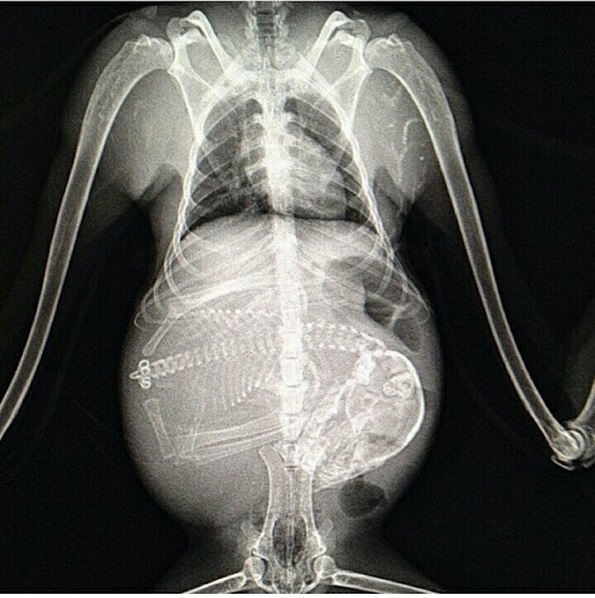

5. Бремено куче

Кучињата се бремени три периоди, а секој период трае по 21 ден. Околу 45-тиот ден возможно е со рендгенски снимки да се открие колку кученца има внатре во стомакот.